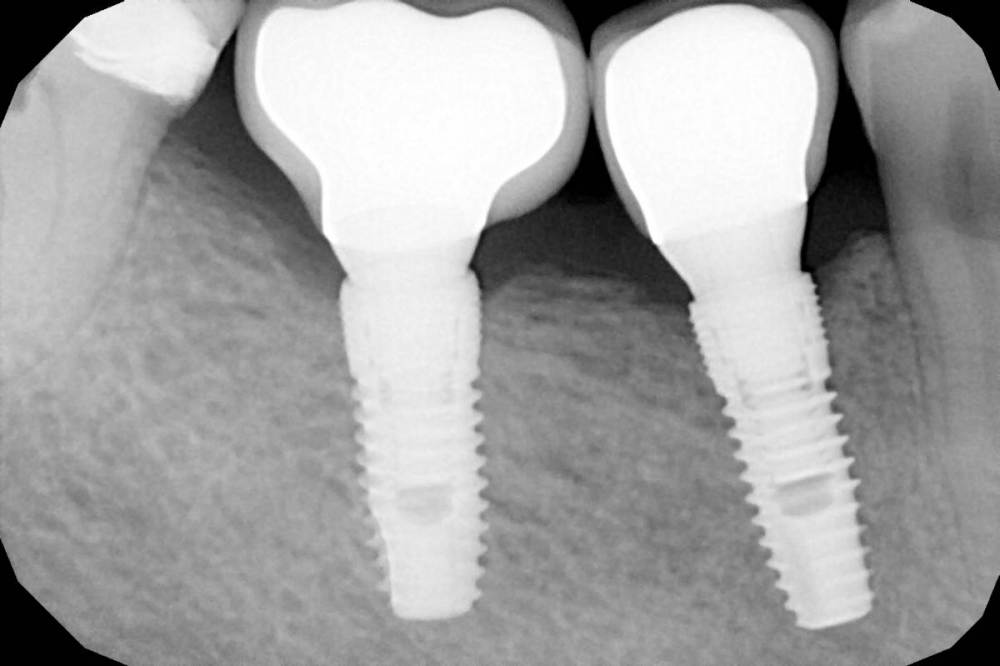

Вот такой финал в итоге получился.

Сосочек восстановлю по Сузуки где-нибудь через месяц.

нет контакта между 4 и 5, будет застревать пища, будет периимплантит